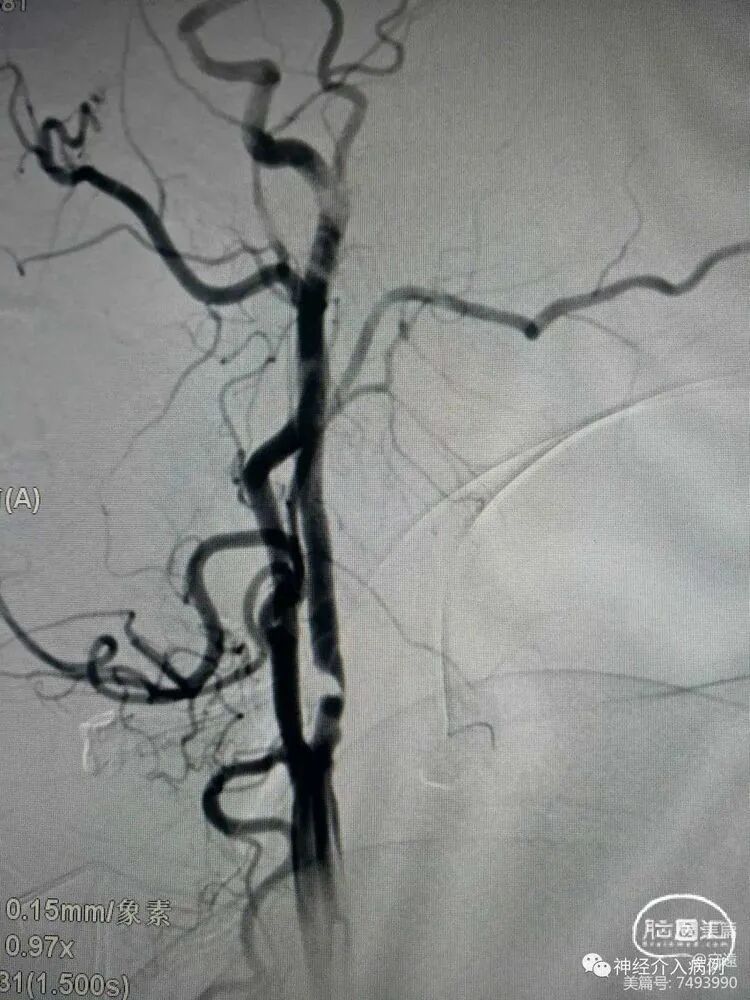

症状性右侧颈内动脉起始段重度狭窄性脑梗死(预扩张+锥形支架置入术)

DSA:前交通动脉未开放,右侧颈内动脉起始段重度狭窄伴溃疡斑块。